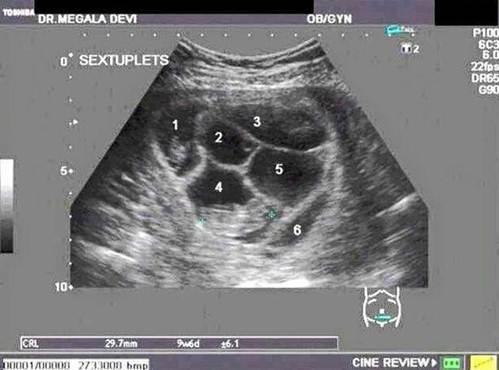

Thế nhưng đó chưa phải là tất cả, khi chị Lauren đi siêu âm, các bác sĩ đã vô cùng sốc khi biết sản phụ không chỉ mang 1 mà là 6 đứa trong bụng. Phôi thai đã tách ra làm 6 và tỷ lệ này là vô cùng hiếm khiến ai nấy đều ngạc nhiên.